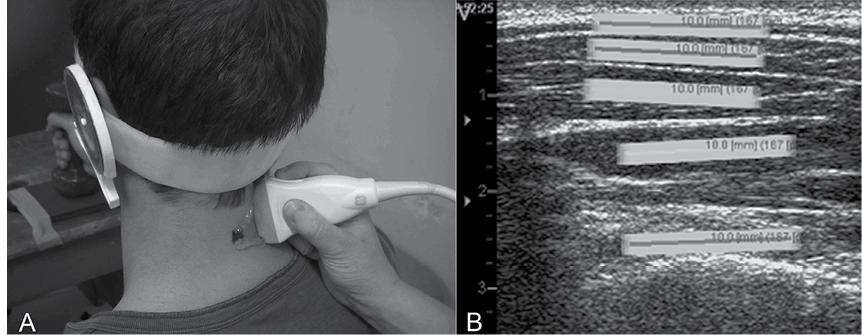

Ultrasound imaging and analysis. US images of the dorsal neck muscles were recorded with a 12.0 MHz linear transducer (38-mm footprint) and US Vividi (GE Healthcare, Horten, Norway) by a single sonographer who was an experienced musculoskeletal physiotherapist with over 3 years of experience in US imaging that includes in excess of 1,000 US registrations of the neck muscles. A 2-dimensional (2D) US image system was used with a high frame-rate of 50 frames/s, operating in B-mode to take recordings of the upper trapezius, splenius, semispinalis capitis, semispinalis cervicis and multifidus muscles (Fig. 1) at the level of the C4 spinous process. A standardized placement of the US transducer was ensured between participants by first positioning it in a transverse orientation at the marked C4 level on the right side to consistently identify the underlying dorsal neck muscle layers and bony landmarks. The transducer was then rotated 90° to the final longitudinal position to the right of the neck midline, as this has been found to be the optimal position to record US videos of dorsal neck muscle contractions (6).

Measurement of muscle deformation and deformation rate. US of muscle results in an interference pattern of acoustic markers (speckle pattern) that can be analysed post-process utilizing the US movie sequence of images (AVI format). This process is termed speckle tracking analysis (STA). During this process a region of interest frame (ROI; 10 × 2 mm) is positioned over a standardized location within the speckle pattern of each muscle in the first frame of the video sequence. The ROI tracks its contained unique speckle pattern frame by frame through the movie sequence. As the contained speckle pattern changes length between frames with muscle activity so does the length of the ROI. This change in ROI length represents muscle deformation. The muscle deformation measure is expressed as the percentage change in the longitudinal median length of the ROI compared with that at rest (% strain). The rate of change in length of the ROI is measured as muscle deformation rate, which is deformation per time unit (expressed as % strain 1/s).